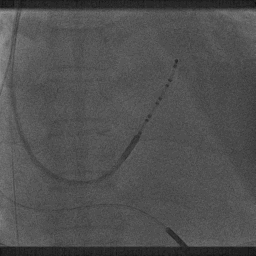

鞘中鞘进入靶血管

超选造影

沿鞘中鞘进四极电极